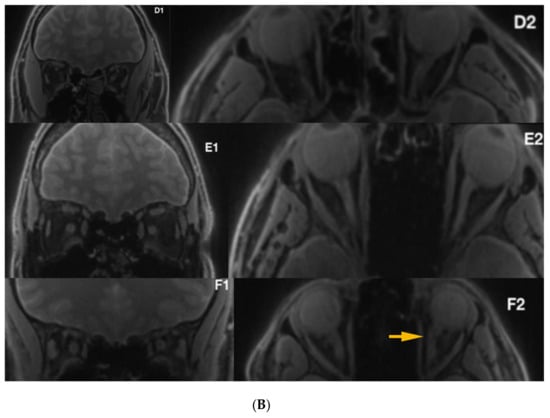

Figure 4.

(A) Silent-MT images in 3 LHON subjects who received Idebenone therapy. The yellow arrows show irregularity within the optic nerve. (B) Silent-MT images in three LHON subjects who received Idebenone therapy. Optic nerve atrophy is not visible in Patient F, (disease duration more than one year), however the yellow arrow shows more tortuous anatomy of the optic nerve, which is consistent with the side of the disease. MT, Magnetization Transfer.

Mean duration of illness in LHON was 12.66 years (1-year minimum, 41 years maximum) and six of the patients (40%) (Figure 4) were treated with Idebenone (the duration of the treatment ranged from 8 months to 15 months). Due to the relatively small sample and quantitative characteristics incompatible with normal distribution, to compare subgroups, a non-parametric Mann–Whitney test (Z) was applied with p < 0.05 set as a statistical significance threshold. Each variable was individually compared between subgroups. Analysis of quantitative dimensions (length, diameters, and surface areas) for left and right optic nerves revealed statistically significant differences for nerve diameter and the surface area measured at the second point (p < 0.05); both parameters were larger for the right nerve (Table 1).

There were no statistically significant correlations between age, duration of illness, and any of the analyzed quantitative measures of nerve anatomy (all p > 0.05). A subgroup of patients receiving Idebenone had significantly larger diameter and surface area of the left nerve at the third measuring point compared with the untreated subgroup (Table 2). These subgroups were similar with respect to age, sex, and duration of illness (p > 0.05).

Quantitative measures of segmented ONSC structures revealed significant changes in nerve diameter and cross-sectional area between left and right optic nerves in the Leber’s hereditary optic neuropathy cohort. The distal part of the left optic nerve was found to be significantly larger in Idebenone-treated patients; this finding in the distal area of the optic nerve was in agreement with several previously published reports [30,31,32,33,34].

Idebenone, a short-chain analogue of ubiquinone, has an ability to shuttle electrons from complexes I and II to complex III. Clinical trials proved the visual benefit after Idebenone treatment and suggest that when used within the time window, it may prevent the retinal ganglion cell death [29,30,31,32,46,47,48,49,50,51,52]. Disease onset among LHON carriers is characterized by acute or subacute painless loss of central vision, which is unilateral at the beginning; the other eye is usually affected within six to eight weeks, which may suggest more advanced abnormalities within the single starting nerve [53]. Our results, obtained with Silent-MT imaging, show significantly larger diameter and surface area of the left nerve at the third measuring point (distal part of the optic nerve), compared to the group not receiving the treatment. Previous research papers reported the presence of hyperintense areas within the distal part of optic nerves [29,50,51,52]. Although the duration of illness among analyzed patients is one year at minimum, (post-acute phase of the disease) there were hyperintense lesions visible within the optic nerves in acquired images, which could suggest the degeneration of the optic nerve as a late complication of the disease.